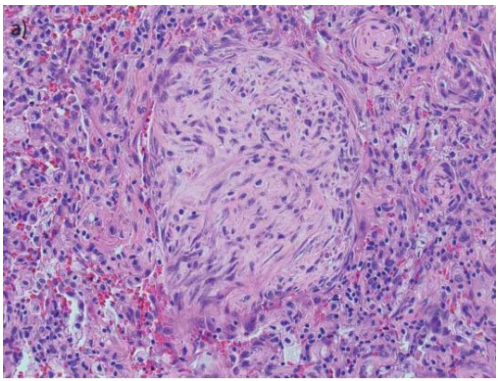

图源:Chest, 2022, 162(1):156-178.从病理方面来讲,OP病变呈斑片状分布;肺泡内、肺泡管见疏松胶原样结缔组织增生,形成Masson小体,主要见于肺泡、肺泡管和终末细支气管;病灶区肺泡间隔有时可见轻微的慢性炎症渗出表现(图19)。

图19 OP的组织病理学

图源:Eur Respir Rev, 2021, 30(161):210094.机化性纤维化包括腔内疏松结缔组织息肉样栓子,突出到远端气腔。肺泡、间隙和肺泡管通常受影响最大,细支气管受影响较小。低倍镜组织学图像(图20A)显示斑片状疏松结缔组织形成的息肉样腔内栓子(粗箭头)区域,突出到远端气道。邻近的肺实质相对正常(细箭头)。图20B示肺泡腔和肺泡管内可见息肉样栓子(粗箭头),但细支气管受累很少(细箭头)。